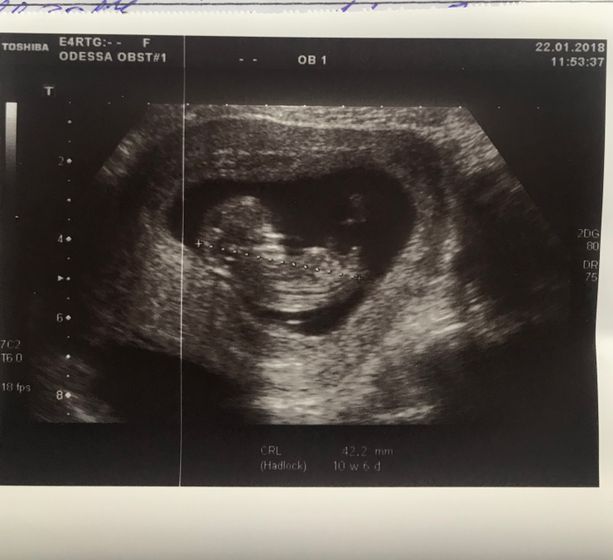

Знаю что некоторые по снимкам УЗИ так заморачиваются что могут распознать пол ребёночка ??♀️, мне подружка твердит по нашей фотке, что у нас мальчишка поселился)) вот только по фотке я всегда думала что это вторая ножка, бедро видно, а она утверждает что это половые принадлежности ??♀️ ) До нашего УЗИ месяц ещё) я как-то особо не парюсь на счёт пола, всё равно первенец))

Это нога или пуповина, не пиписька явно, тем более в 11 недель у них там ничего не отличается.

Мне кажется что это согнутая ножка а не половой бугорок

Ну если УЗИ было в 11 недель тем более, явные половые признаки у них формируются с 12 недель, у мальчиков появляется бугорок, поэтому это скорее всего согнутая ножка))

Ну вообще да, похоже у вас на половой бугорок и вверх, на мальчика похоже